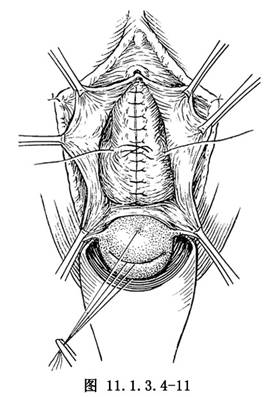

(5)再在膀胱頸部,以2-0鉻制腸線作橫8字形褥狀縫合1針,以提取和縮窄陰道膀胱頸(圖11.1.3.4-11)。